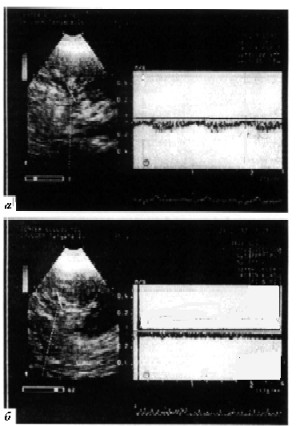

Рисунок 15. Кровоток в почечной вене:

а - до выполнения бхуджангасаны, б - во время выполнения упражнения.

Рассмотрение динамики параметров венозного оттока от почки (табл. 7 и рис. 15) свидетельствует о том, что скорость кровотока по почечной вене в фазу систолы правого желудочка VS при выполнении позы "кобры" не менялась (-14,4±1,4 и -16,0±1,8 см/c, p<0,05), значимо возрастал отток в систолу предсердия VA (с -4,5±1,4 до -10,2±1,2 см/c, p<0,01). Частота сердечных сокращений ЧСС возросла с 78,5±2,9 до 112,8±4,3 уд/мин, p<0,001. Эти показатели после выполнения упражнения возвращались на исходный уровень.